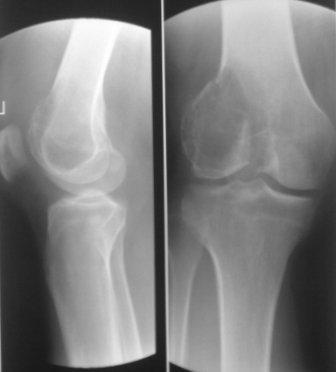

Обратился мужчина 32 лет с жалобами на боли в обл. внутреннего мышелка левого бедра. Боли беспокоят около шести месяцев, лечился дома всякими мазями и т.д. 2 неделя назад упал , и после этого боли с каждым днем усиливаются. Местно определяется резкая болезненность в обл. мышелка бедра, явление не выраженного синовита, ограничение движения в коленном суставе, мягкотканый компонент опухоли не определяется, лимфоузлы не увеличены,Р-скопия легких без патологии,клинико-биохимические анализы в пределах нормы. Гистология- гигантоклеточная опухоль.

Направил в онкологический центр, рекомендовали резекцию и ревизионное эндопротезирование коленного сустава, от которого больной отказался и опять вернулся к нам, временно фиксировали гипсовой повязкой.

Уважаемые коллеги можно ли помочь больному, т.к. на практике были, что после перелома опухоль рассосалась и переломы срослись! Или может быть аутопластика и фиксация перелома?